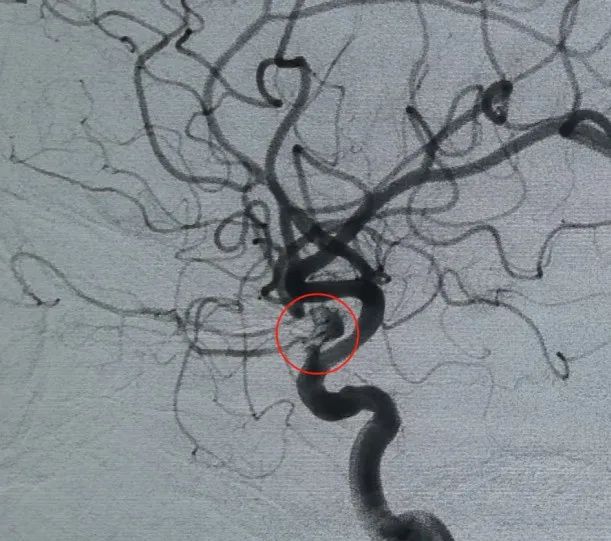

Dostęp naczyniowy ustalono poprzez nakłucie tętnicy udowej i Perdenser®Cewka 3D o wymiarach 6mm × 20 cm została po raz pierwszy rozmieszczona w celu utworzenia kosza, uzyskując stabilną apozycję ściany i zapewniając bezpieczne podparcie wewnątrzskarbowe. Następnie wstawiono Perdenser®Cewka 3D 6mm × 15 cm, aby zakłócić przepływ krwi w płatowym worku potomnym.

Perfiller®Cewka ekspansywna 3mm × 6 cm i Perfiller®Następnie umieszczono rozszerzalną cewkę o wymiarach 3mm × 2 cm, aby zakończyć okluzję szyjki. Następnie Nuva®Flow Diverter (TJED-D-5.0-16) został dostarczony i rozmieszczony w poprzek szyi tętniaka. Dalsza angiografia zarówno w widoku przednio-tylnym, jak i bocznym potwierdziła doskonałe pokrycie, dobre położenie ściany i wyraźną przezroczystość promieniową, z wyraźną stagnacją kontrastu.